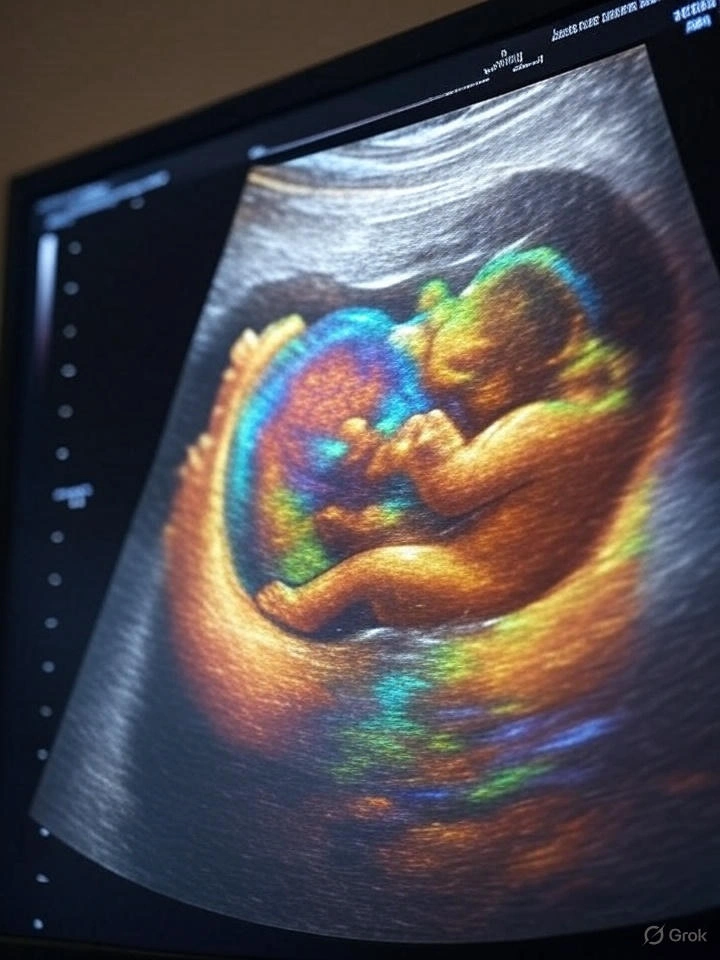

لا يوجد جدول رسمي معتمد ثابت لنسبة الهرمون في التوأم، لكنها غالبًا ما تكون في أعلى حدود المعدلات الطبيعية. مثلًا، في الأسبوع الخامس قد تتجاوز النسبة 7000 إلى 20000 وحدة دولية لكل لتر. التحليل الرقمي يوضح هذه النسبة بدقة، لكنه لا يؤكد التوأم دون فحص بالموجات فوق الصوتية.

تختلف النسبة بشكل كبير من سيدة لأخرى. بعض التجارب تشير إلى أن النساء اللاتي حملن بتوأم كانت نسبتهن في الأسبوع الرابع بين 1000 و4000 وحدة، وفي الأسبوع الخامس قد تصل إلى 15000 أو أكثر. ومع ذلك، لا يمكن الاعتماد فقط على النسبة لتحديد عدد الأجنة. يجب الانتظار للتصوير بالموجات الصوتية لتأكيد وجود أكثر من جنين.